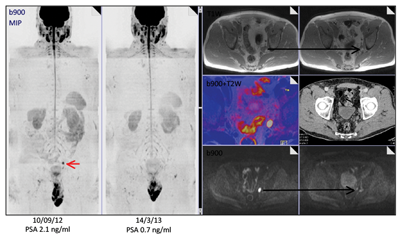

A 66-year-old man presented with a locally advanced T3b N1 prostate cancer in 2011, with an initial PSA of 33. He was treated with robotic prostatectomy and lymph node dissection followed by adjuvant prostate bed radiotherapy. Although immediate post treatment PSA levels were undetectable he had a PSA relapse in September 2012 to 2.1. Whole body MRI and Choline PET showed an apparent isolated left iliac lymph node recurrence (Figure 4). He went on to receive stereotactic radiotherapy (33Gy in 3 fractions to the lymph node - Figure 5). Follow-up imaging has shown a complete radiological response within the treated node. Eighteen months after treatment his PSA has started to rise again and most recent imaging has shown the development of a lymph node on the opposite side of the pelvis with no other sites of disease. He subsequently had further stereotactic radiotherapy to the right pelvic side wall nodes in July 2014. His PSA has dropped to 0.02 on his most recent check in January 2015.

Figure 4: Isolated pelvic lymph node recurrence on whole body MRI and Choline Pet and response to treatment.